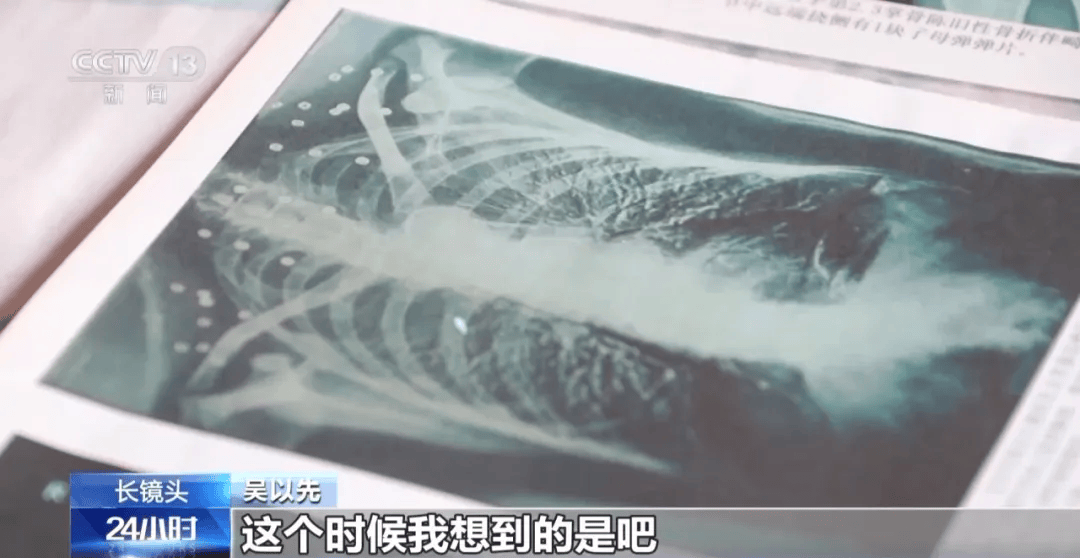

这张照片

是今年82岁的吴以先老人

拍摄的一张CT照

吴以先的颈部和腹部

共分布着33枚弹片

但是打进身体里的弹片

一直留在了体内

他体内的弹片都没有取出

与吴以先身上那33枚弹片